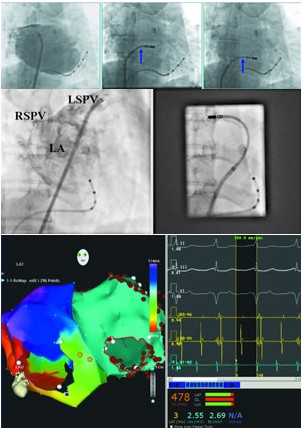

要点3 初始穿刺后左心房(肺静脉)造影非常重要,可评价穿刺点位置是否理想,并指导选择更好的穿刺点重新穿刺(图1)。

减少X线投照

对术者而言,右前斜位(RAO)比左前斜位(LAO)减少60%的X线投照。另外,缩小影像、缩小光圈,仅显示左心房,可减少数倍曝光量,对医患都有利(图2)。

左右两侧前庭顶部曾经是消融电极不易理想贴靠的部位,但是通过特殊导管操作构型后这些部位操作反而最容易,即“反弯法”操作(图2)。

图1 根据初次房间隔穿刺位置调整再次穿刺位置

A 首次房间隔穿刺后左房造影;B 导管打弯后回撤受阻点(箭头)为房间隔穿刺点,位置较高 ;C 再次穿刺后可见房间隔穿刺点(箭头)位置较低,有利于导管在左心房的操作。

A 左上肺静脉(LSPV)造影RAO 30° X线影像, 可见左心房(LA)顶部及右上肺静脉(RSPV);B 消融导管反弯法到位, 可见消融导管指向右侧(图中左侧),鞘管指向左侧(图中右侧)。图A影像约占全光圈面积的60%,图B约占全光圈面积的25%。

左房消融肺静脉隔离及左房顶部线、二尖瓣环峡部线和少量CFAE消融后房颤转变为规律的心动过速, 激动顺序标测证明为三尖瓣环峡部依赖的三尖瓣环房扑(左图的左侧彩色图), 激动顺序为红黄绿蓝紫绕三尖瓣环的环形运动。